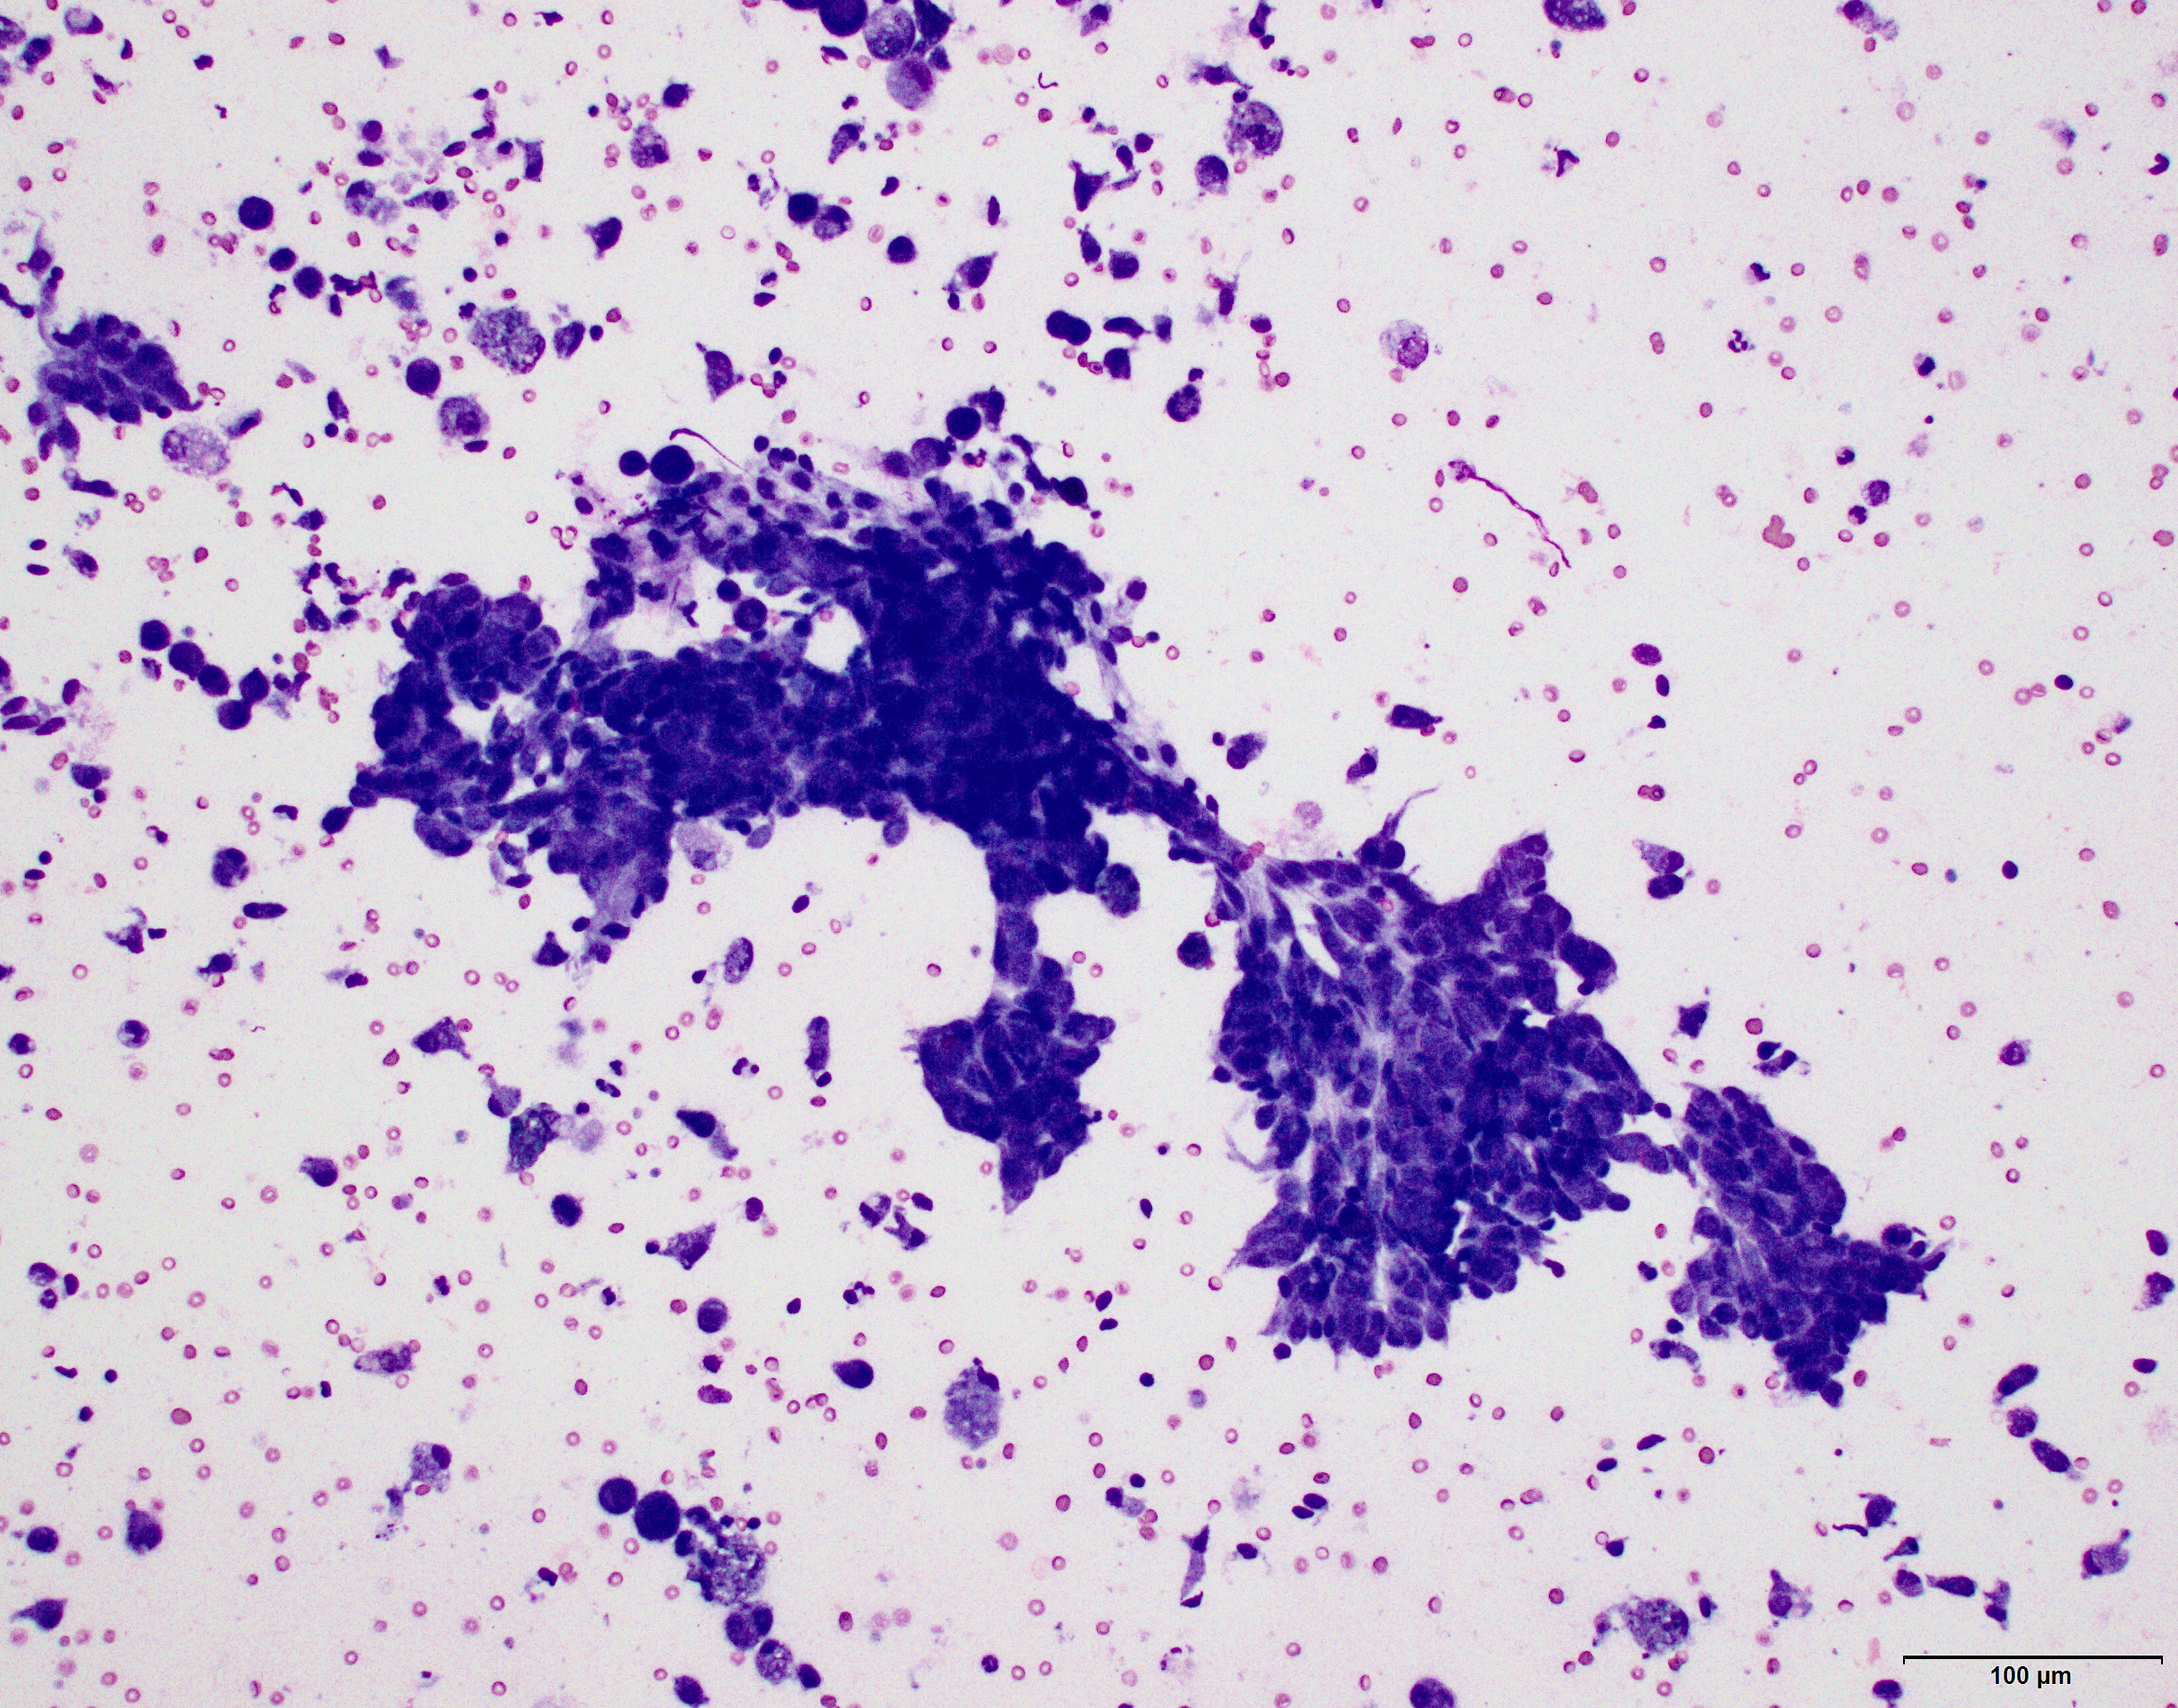

Cytology from fine needle biopsy of large mammary mass in left 5th gland:

Low Power view

High Power view